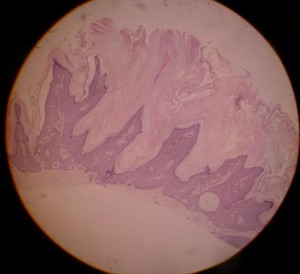

C. Hyperkeratotic (AHCS) {Pierson, 2003}

Also called papillomatous, or digitate, or serrated SK, this type is histologically opposed to the acanthotic type.

In the epidermis, hyperkeratotic SKs can display acanthosis, but are characterised by an important papillomatosis and hyperkeratosis. The epidermal keratinocyte projections towards the stratum corneum have a church-spire appearance.

Squamous like cells are more numerous than basaloid cells. Abundant pigmentation is typically absent. Pseudocysts rarely keratinize.

Acanthohyperkeratotic type of SK: the sharp projections adjoining the stratum corneum are called church spires